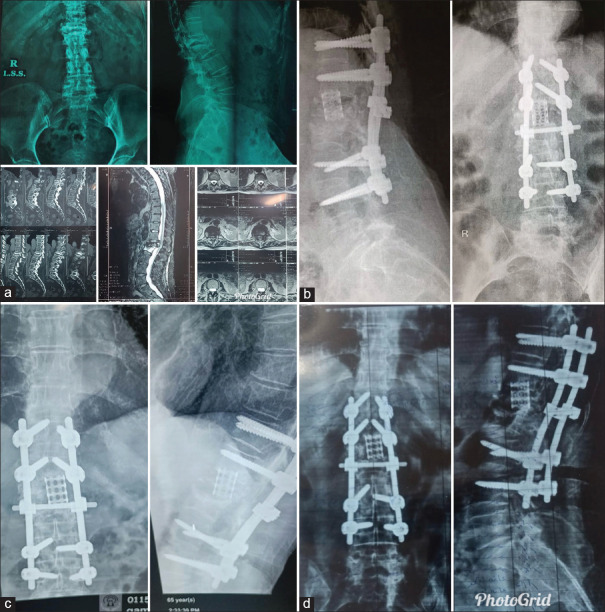

Short-term assessment of functional outcomes and quality of life after thoracic and lumbar spinal metastasis surgery.

Patients and methods: In this prospective cohort study, a total of 33 patients with thoracic and lumbar spine metastases who underwent surgical management between November 2021 and August 2023 were followed up for 1 year or until death. Oswestry Disability Index and the Eastern Cooperative Oncology Group Performance Status were used for the functional outcome; QOL was assessed using European Quality of Life 5-Dimensions (EuroQOL-5D). Scores were recorded preoperatively, 4 weeks postoperatively, and 6 and 12 months postoperatively.

Results: The mean age was 52.12 ± 13.4 years (range: 23-70 years), 22 (66.7%) were females, and 11 (33.3%) were males. Patients were divided into three groups according to the revised Katagiri score: 12 (36.4%) patients were at low risk (0-3), 18 (54.5%) patients were at intermediate risk (4-6), and 3 (9.1%) patients were at high risk (7-10). The mean survival was 5.44 ± 3.46 months (range 1-13), and there was no perioperative death (within 1 month postoperative). Sixteen (48.5%) patients survived for more than 1 year and 17 (51.5%) patients died from different causes related to the natural history of tumor metastasis.

Conclusion: Following surgical treatment of the spinal metastases, improvements in QoL and functional results were seen in the short-term. For patients with a projected life expectancy of longer than 3 months, surgery is a good alternative.